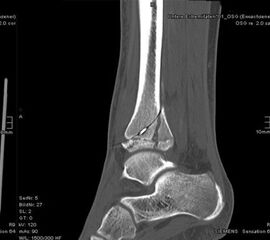

Computertomografie

Die Computertomografie liefert die höchste Auflösung für knöcherne Verletzungen und die Untersuchung dauert nur wenige Sekunden. Nachteilig ist die hohe Strahlenbelastung, die bei einem Vielfachen von konventionellen Röntgenbildern liegt. Bei komplexen Gelenksfrakturen hat die Computertomografie aber auch beim Kind ihre Berechtigung und erleichtert die Planung der Rekonstruktion.

Der teilweise komplexe Frakturverlauf bei Übergangsfrakturen lässt sich im CT zuverlässig darstellen 10. Der erfahrene Untersucher kann bereits mit Röntgenaufnahmen des Sprunggelenks in zwei Ebenen in Verbindung mit zwei 45° Schrägaufnahmen sehr umfassende Aussagen zum Frakturverlauf treffen (v. Laer 2013), die Präzision und Aussagekraft der Computertomografie ist aber zweifelsohne überlegen und wird von den meisten Behandlern bevorzugt 11, auch wenn sich zu diesem Thema in der Literatur eine teilweise sehr emotional geführte Diskussion findet. Einigkeit hinsichtlich der Indikation für ein Schnittbildverfahren besteht bei Triplane-Frakturen, wenn Zweifel darüber bestehen, inwieweit die metaphysäre Fraktur den tragenden Gelenkanteil tangiert 12.